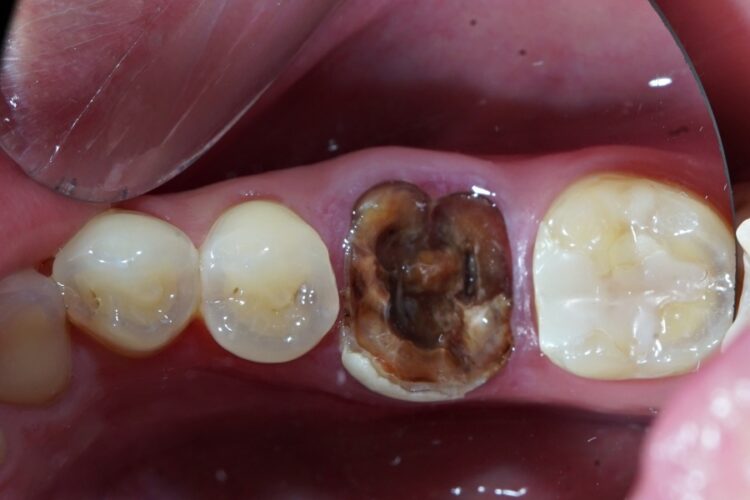

Вихідна ситуація: пацієнтка Л. звернулася щодо виготовлення коронки на зуб в одне відвідування.

При огляді в порожнині рота між коренями нижнього шостого зуба добре видно тріщину. Для уточнення ми провели рентгенологічне дослідження, що підтвердило порушення цілісності коренів зуба. Зуб не підлягав відновленню коронкою. Пацієнтці рекомендовано видалення з одномоментною імплантацією.

В даному випадку наявні сприятливі умови для застосування одномоментного способу:

• відсутність запалення у кістці в ділянці коренів;

• відсутність запалення слизової оболонки в місці проведення операції;

• хороший стан зубів, немає вогнищ інфекції (карієс, інші зруйновані, тощо);

• достатній обсяг кісткової тканини.